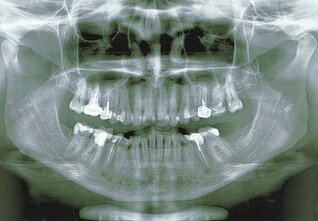

Dantys – lakmuso popierėlis, matmuo. Greičiausiai dauguma turi savo dantų, žandikaulių rentgeno nuotraukų. Pažiūrėkite į jas atidžiai. Būtų puiki paroda, antropologinė. Jie kaip niekas kitas galėtų papasakoti visą žmogaus istoriją, kaip kito patys dantys, santykis su jais visose epochose. Juk aišku, kad kilmingųjų dantys buvo geresni (nežinau, ar šis žodis čia tinka) – valgė daugiau mėsos etc., už eilinių mirtingųjų, kurių dantys buvo labiau nudilę, panašūs į stirnų, nes nuolat turėjo malti grūdus, ropukes ir žoles... Ir iš karo kaip grobį parsinešti nukauto priešo gerus dantis buvo norma.